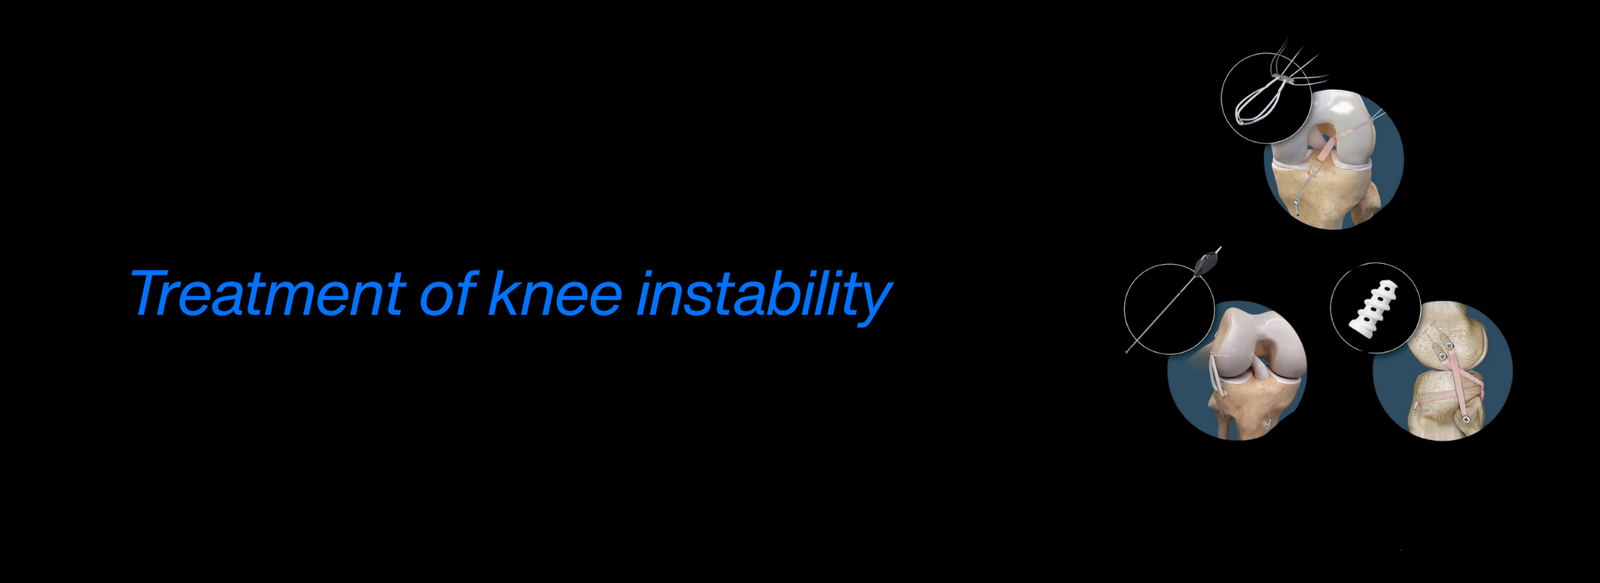

Fellowship in Arthroscopy: Expertise in minimally invasive surgery to diagnose and treat joint conditions, such as torn cartilage or ligament injuries, particularly of the knee, shoulder, and hip.

AO Recon Hip & Knee Arthroplasty: Advanced training in reconstructive surgeries, particularly hip and knee replacements, for patients suffering from degenerative diseases or complex injuries.